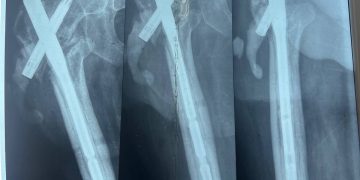

Пациентом стал 32-летний Илья из ЛНР, мобилизованный 25 февраля 2022 года.Сержант получил тяжелейшее осколочное ранение правого бедра под Херсоном 28 августа 2022 года.За три с половиной года боец прошёл через десять госпиталей, включая ЦВКГ им. Вишневского в Москве и ВМА им. Кирова в Санкт-Петербурге, перенёс множественные операции по удалению некрозов и остеосинтезу.

К моменту увольнения со службы в июле 2024 года основная проблема оставалась нерешённой: правая нога была короче левой почти на 9 сантиметров. Стандартное протезирование в такой ситуации неэффективно.

Хирургам ЛРКБ предстояло работать в рубцово-изменённых тканях после десятка предыдущих вмешательств, устранить очаги инфекции и с помощью специальных ревизионных компонентов восстановить биологическую ось конечности и вернуть ей физиологическую длину.